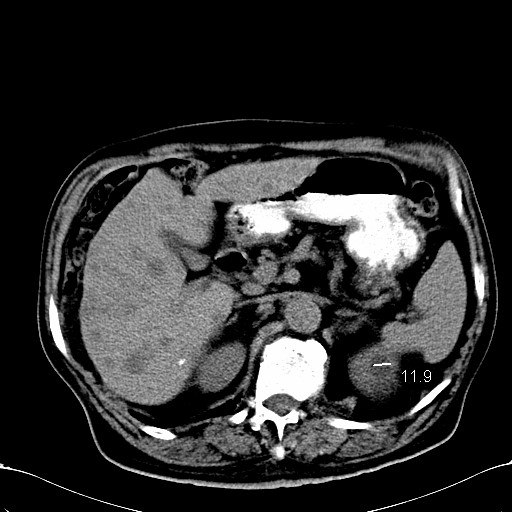

标题: CT28270:胰管扩张,肝多发占位 [打印本页]

标题: CT28270:胰管扩张,肝多发占位

患者,男,75岁。

肝脏多方低密度结节,边缘模糊,考虑多发转移,胰管明显扩张,建议增强扫描钩突情况

肝脏多发低密度灶,胰头似呈低密度,胰管扩张,建议增强,

胰管显著扩张,但胆总管未见扩张征象,不太符合胰头占位!考虑慢性胰腺炎.胃窦占位并肝内转移可能!mrcp胃镜增强一起上!